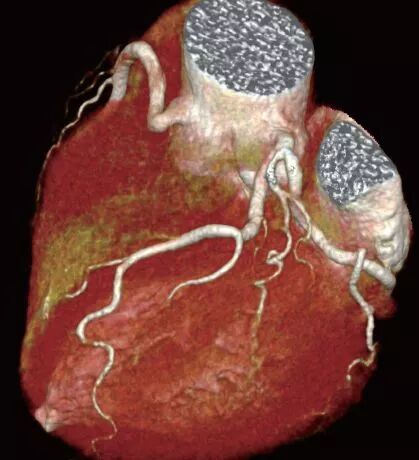

高质量心脏冠脉成像

冠心病是危害人类健康的首要杀手,可靠的早期筛查及手术后复查极为重要。

传统的螺旋CT由于仅有一套X射线发生装置和一套探测器系统,所以在扫描高速运动物体时(比如冠状动脉)会显得力不从心。而双源CT系统能够以83毫秒(1000毫秒=1秒)的时间分辨率采集与心电图同步的心脏和冠状动脉图像。

西门子双源CT(SOMATOM Drive)机架内置两套球管及探测器系统,扫描速度比传统螺旋CT提高了一倍,可在一次心跳内完成心脏扫描,从而实现高质量、低辐射冠脉成像。可让高心率,心率不齐的患者快速完成心脏检查。